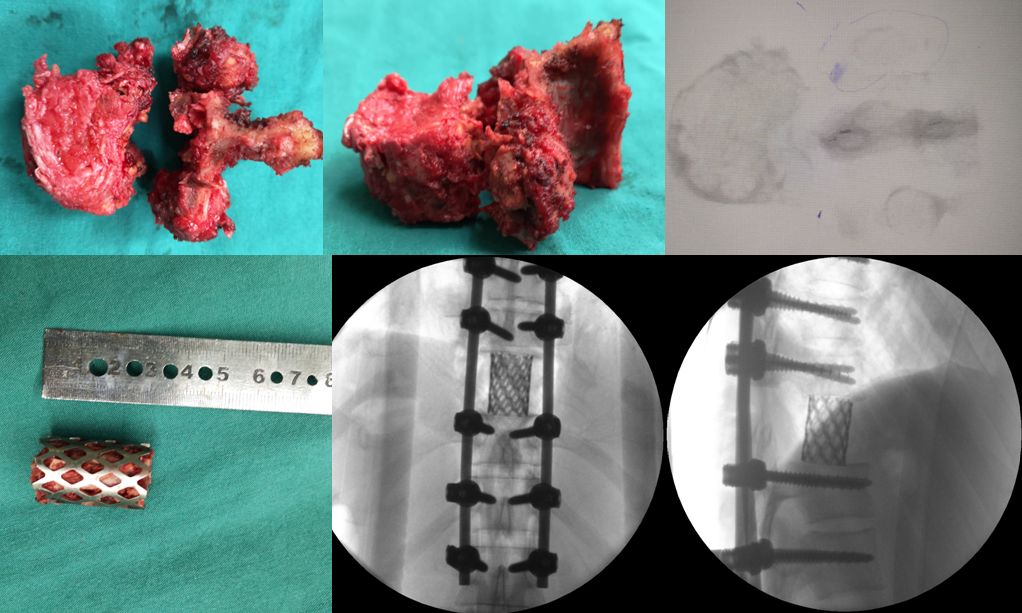

因为肿瘤周围紧挨着神经、脊髓和血管,手术既要保持肿瘤组织的完整切除,又不能牺牲重要结构,因此每一步都需要小心翼翼,张顺聪教授和丁金勇教授紧密合作,不敢有一丝懈怠,将肿瘤椎体一点一点的分离而不损伤周边正常组织。手术整整进行了9小时10分钟,在张顺聪教授和丁金勇教授专业细致的操作下,患者最终有惊无险的完成整个手术,肿瘤椎体被完美的切除,术后疗效满意。

脊柱肿瘤被完美切除,内植物位置满意